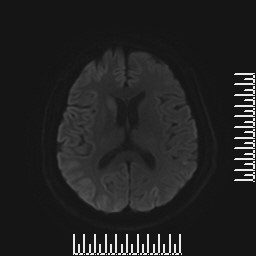

查体:问答及查体部分合作,反应迟钝,定向力定时力差,眼球运动检查,仅可向上及向右转动,四肢肌张力高,以右下肢为轻,可见左上肢不自主抖动,肌力检查、共济、感觉检查不配合。 辅助检查:颅脑DWI示右侧尾状核信号增高,双侧颞顶枕叶脑回样增高,脑电图提示背景节律无枕区优势,全导连续性双相或三相慢波发放,后头部为甚,睡眠周期性三相波少见,全导连续慢波活动,脑脊液常规、生化及培养未见明显异常,14-3-3蛋白阳性